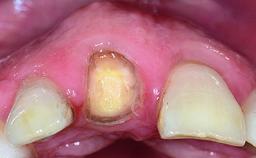

Replacement of a Failing Upper Left Central Incisor: Immediate Placement of an RC Bone Level Implant and Provisionalization

A healthy 23-year-old female patient was referred for a consultation on replacing tooth 21 with an implant-supported restoration. The patient had recently moved to the area and reported a history of endodontic and periodontal treatment for tooth 21. The tooth had been deemed non-restorable by her previous periodontist but since she was going to be moving, he recommended consulting to a dentist in her new city to continue her treatment. A review of her medical history yielded no significant findings and no known drug allergies. The analysis of her smile revealed a medium to high symmetrical smile line and a slightly discolored tooth 21.

Loading Protocol Immediate

Provisional Implant-Supported Prosthesis Prosthodontic margin < 3 mm apical to mucosal margin Prosthodontic margin < 3 mm apical to mucosal margin